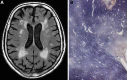

Vascular cognitive impairment (VCI) [vascular cognitive disorder (VCD), vascular dementia] describes a continuum of cognitive disorders ranging from mild cognitive impairment (MCI) to dementia, in which vascular brain injury involving regions important for memory, cognition and behavior plays an important role. Clinical diagnostic criteria show moderate sensitivity (ca 50%) and variable specificity (range 64-98%). In Western clinical series, VaD is suggested in 8-10% of cognitively impaired elderly subjects. Its prevalence in autopsy series varies from 0.03 to 58%, with means of 8 to 15% (in Japan 22-35%). Major types of sporadic VaD are multi-infarct encephalopathy, small vessel and strategic infarct type dementias, subcortical arteriosclerotic leukoencephalopathy (SAE) (Binswanger), multilacunar state, mixed cortico-subcortical type, granular cortical atrophy (rare), postischemic encephalopathy, and a mixture of cerebrovascular lesions (CVLs). They result from systemic, cardiac and local large or small vessel disease (SVD); their pathogenesis is multifactorial. Hereditary forms of VaD caused by gene mutations are rare. Cognitive decline is commonly associated with widespread small ischemic vascular lesions involving subcortical brain areas (basal ganglia and hemispheral white matter). The lesions affect neuronal networks involved in cognition, memory, and behavior (thalamo-cortical, striato-subfrontal, cortico-subcortical, limbic systems). CVLs often coexist with Alzheimer-type lesions and other pathologies; 25-80% of elderly demented show mixed pathologies. The lesion pattern of "pure" VaD differs from that in mixed dementia (AD + CVLs) suggesting different pathogenesis of both phenotypes. Minor CVLs, except for severe amyloid angiopathy, appear not essential for cognitive impairment in full-blown AD, while both mild AD-type pathology and SVD may interact synergistically in promoting dementia. However, in a large percentage of non-demented elderly individuals, both AD-related and vascular brain pathologies have been reported. Despite recent suggestions for staging and grading CVLs in specific brain areas, due to the high variability of CVLs associated with cognitive impairment, no validated neuropathological criteria are currently available for VaD and mixed dementia. Further clinico-pathological studies and harmonization of neuropathological procedures are needed to validate the diagnostic criteria for VaD and mixed dementia in order to clarify the impact of CVLs and other coexistent pathologies on cognitive impairment as a basis for further successful therapeutic options.